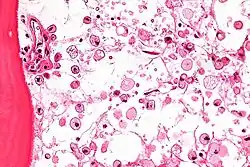

أمراض الاختزان في الجسميات الحالة (بالإنجليزية: Lysosomal storage diseases) هي مجموعة من حوالي 50 مرضا استقلابيا نادرا وراثيا ناتجة من خلل في وظائف الجسميات الحالة.